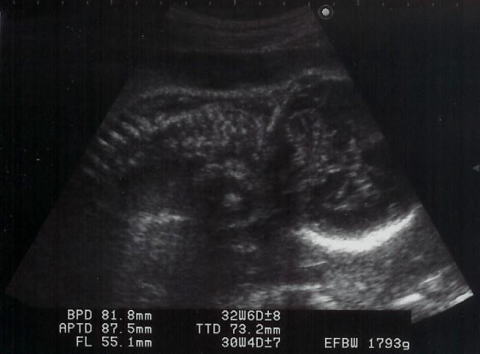

|  shigeru、3週間ぶりの健診です。ママは後期の検査がありました。ここのところ、ママは夜眠れない日々が続いています。そのことをお医者様に話したら・・・「(shigeru)重さは1793g。重くなったんだもの、眠れないのは仕方ないですよ。」と。ママは眠いときに眠れば、夜に眠れなくても大丈夫とのこと。お医者様は「かわいいわね〜」とエコーをみながら言いましたが、ママには骸骨か宇宙人にしかみえません。でも、shigeruは大きくなりましたね。ほっぺがふっくらしているのがエコーでもわかるのですから。

右が頭で足を抱えて下を向いてます。

顔面アップ。右が頭で、こちらを向いています。